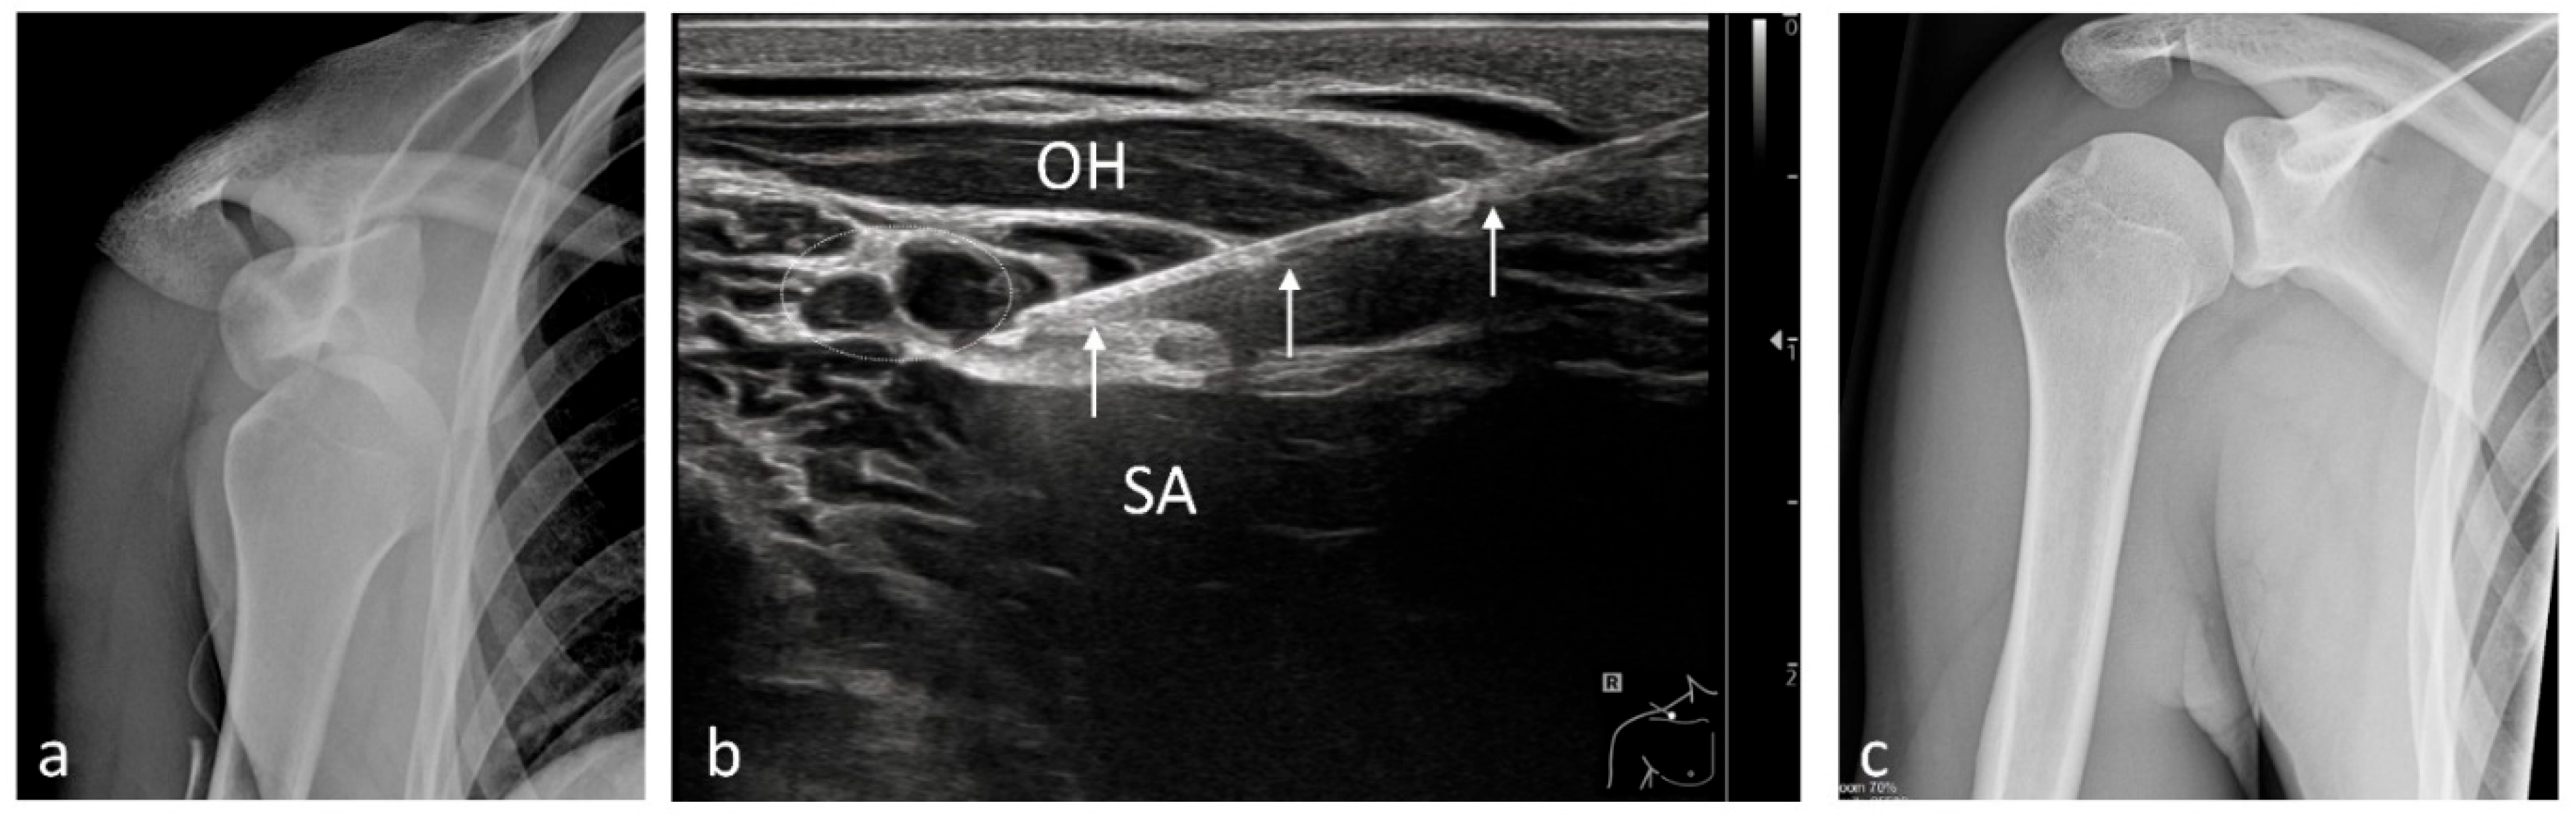

| Shoulder | 99 | Brachial plexus block (interscalene)/3–5 |

| Shoulder prosthesis | 5 | Brachial plexus block (interscalene)/3–5 |

| Rotator cuff pathology | 63 | Brachial plexus block (interscalene)/3–5 |

| Shoulder osteoarthritis | 19 | Brachial plexus block (supraclavicular)/10 (5)–20 |